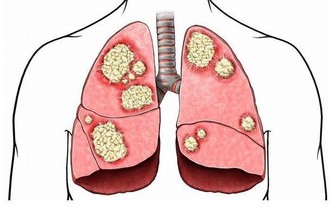

【3】膀胱疾病

晚上頻繁起夜上廁所,有可能是膀胱疾病引起的,膀胱保持正常功能,才可以儲存尿液。

但如果莫名其妙出現尿頻尿急,夜尿增多,很可能是膀胱出現了惡性腫瘤或者是膀胱結石,導致膀胱儲存尿液的能力降低,伴隨著排尿頻繁的表現。